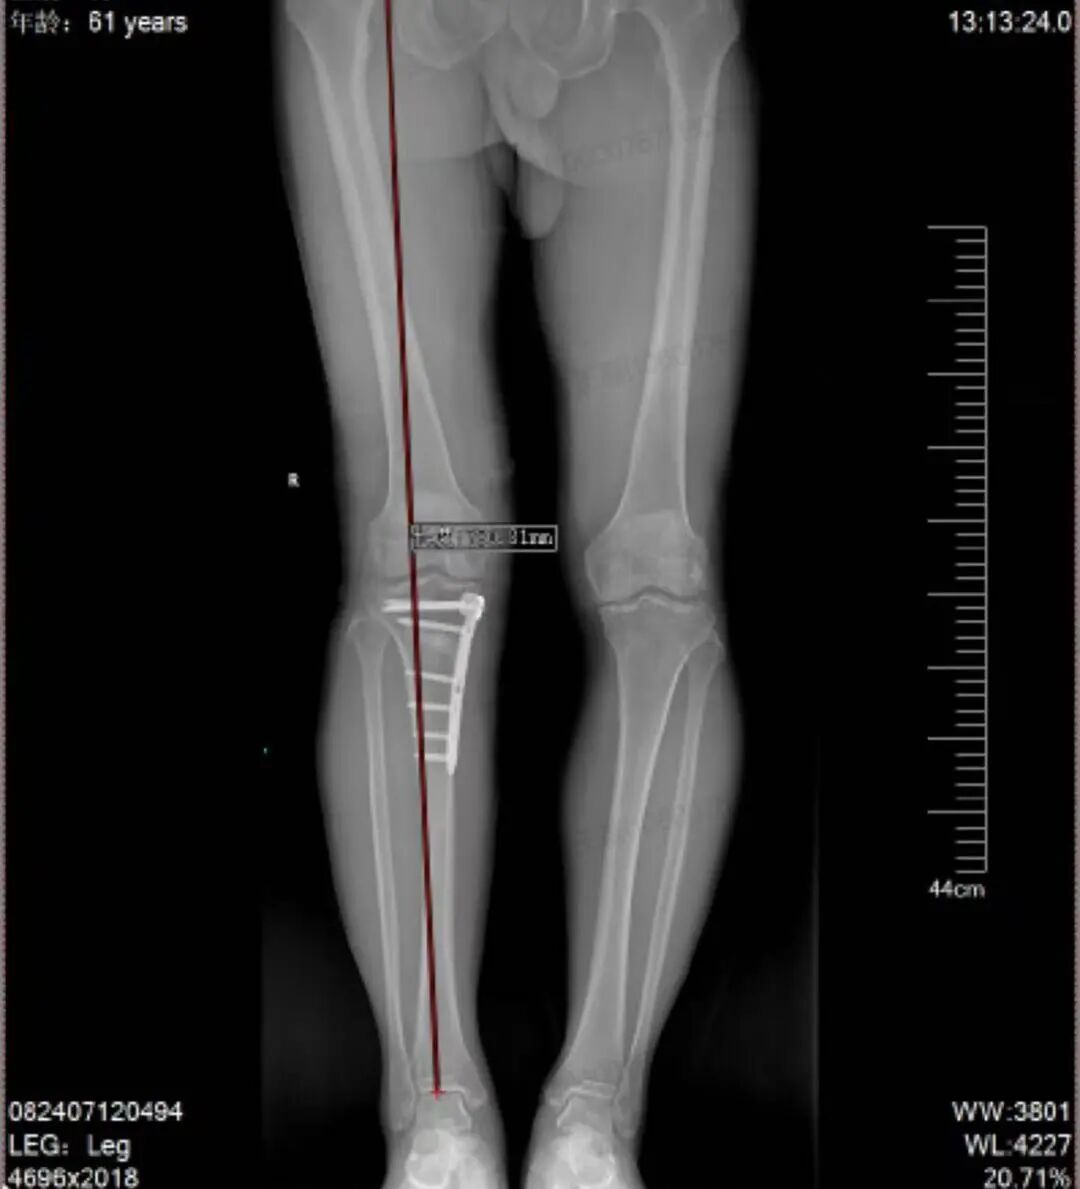

面对李先生的病情,若直接进行膝关节置换,虽能解除疼痛,但对于活动需求较高的患者而言,意味着将失去宝贵的原生关节。王磊主任团队经过综合评估,为他制定了个性化的「保膝」方案——胫骨高位截骨术(HTO)。

王磊主任解释,HTO 手术的原理类似于「矫正一棵长歪的树」。它并非替换关节,而是通过精确调整胫骨上端的角度,将膝关节的承重主力线,从已磨损严重的内侧区域,转移至相对健康的外侧软骨区。

这样不仅立刻缓解了疼痛,还 为受损的内侧软骨创造了自我修复的宝贵机会,从而有效延缓了关节的退化进程。